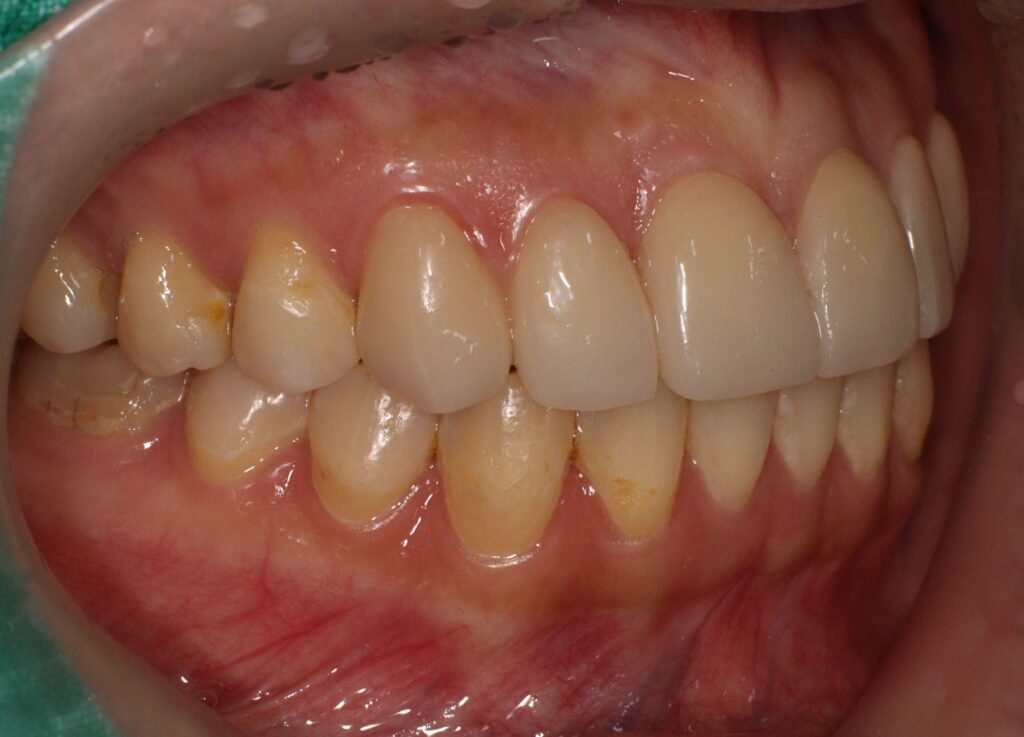

먼저 심미적인 개선이 가장 중요한

위쪽 송곳니부터 송곳니까지

총 6개의 전치부에 대해 e.max empress

라미네이트 베니어를 적용하였습니다.

이를 통해 치아의 색상과 형태를

자연스럽게 개선하고,

전체적인 조화를 맞추는 데 중점을 두었습니다.

치료 후에는 치아의 색상과 배열,

형태가 자연스럽게 어우러지며

환자의 만족도를 높일 수 있었습니다.